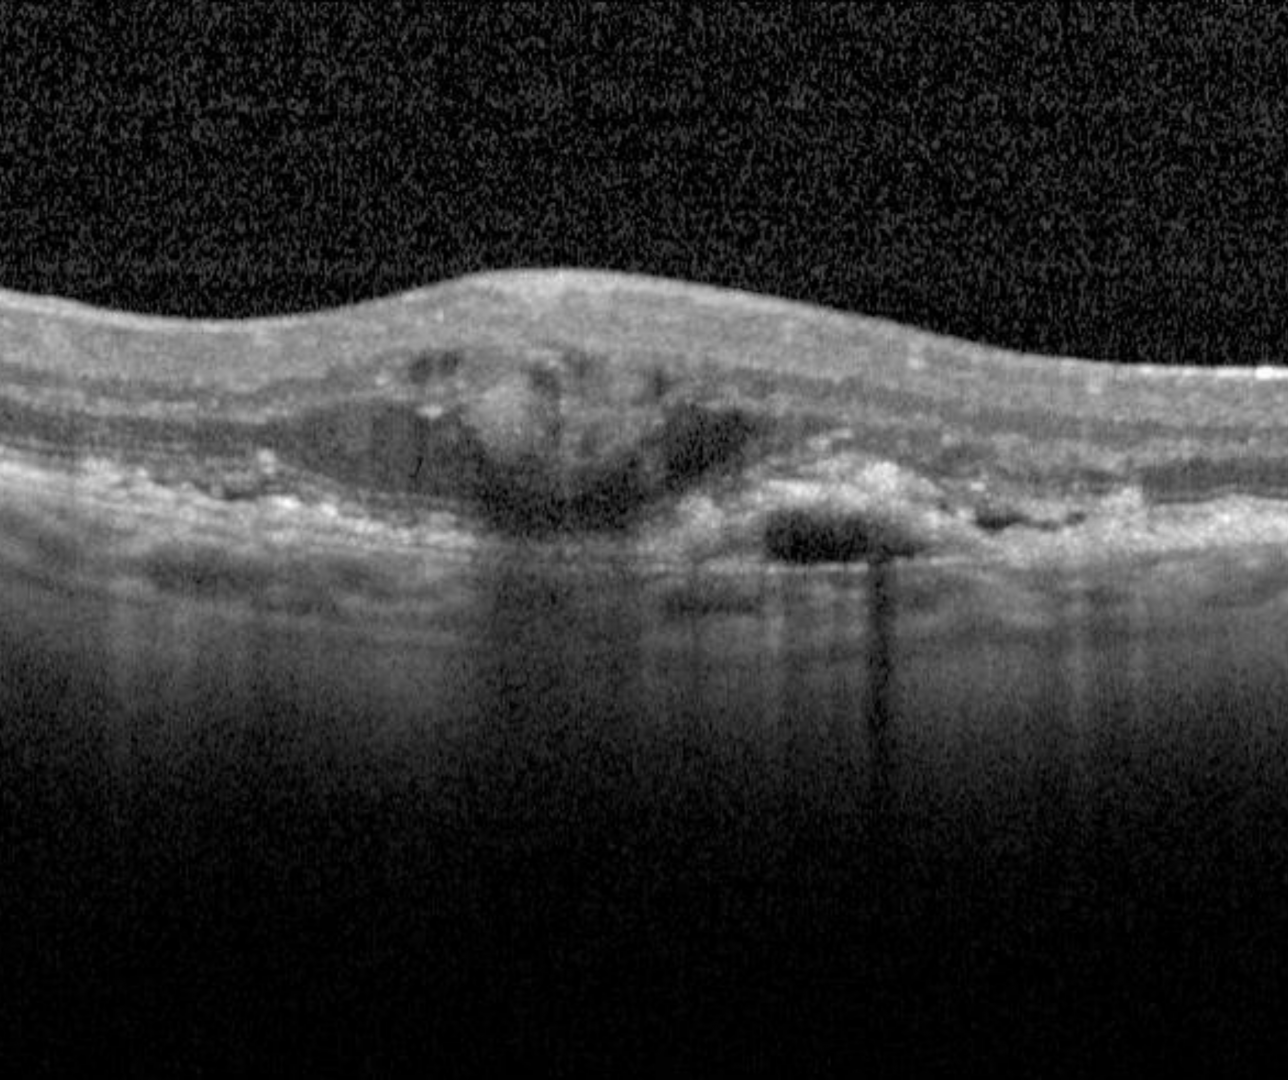

Some key findings on OCT imaging indicating the likely presence (but are not a definitive diagnosis) of neovascular membrane include:

- RPE detachments - these present as broad elevations of the RPE band anterior to Bruch's membrane with hypo- or mixed internal reflectivity

- Intraretinal, subretinal or sub-RPE fluid

- Scarring or fibrin like deposits

- Subretinal haemorrhage and/or

- Hard exudates